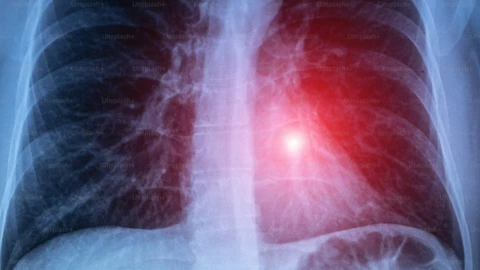

Las autoridades sanitarias detallaron que la tuberculosis respiratoria es una infección contagiosa causada por la bacteria Mycobacterium tuberculosis que afecta principalmente los pulmones, transmitiéndose por el aire al toser o estornudar. Te compartimos los síntomas:

La tuberculosis respiratoria puede ser una enfermedad grave si no se detecta y trata a tiempo. Sin atención médica adecuada, la infección puede avanzar y provocar complicaciones severas en los pulmones e incluso extenderse a otras partes del cuerpo.